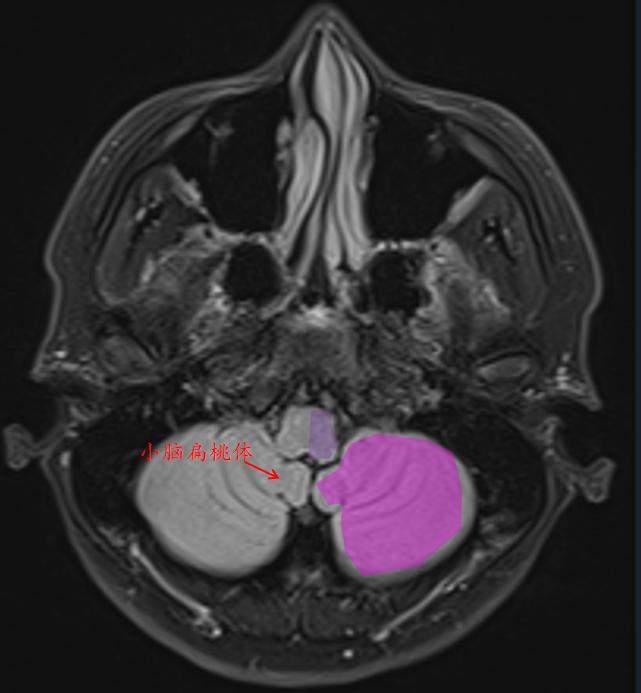

这就是常规医院扫描的t2-flair的相似层厚层间距的图像。

人脑分为:大脑(又称端脑),间脑(背侧丘脑、后丘脑、上丘脑、下丘脑、低丘脑)、小脑和脑干(中脑、脑桥、延髓)。